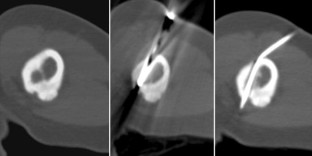

Abb. 1

Abb. 2

Abb. 3

Abb. 4

Abb. 5

Abb. 6

Abb. 7